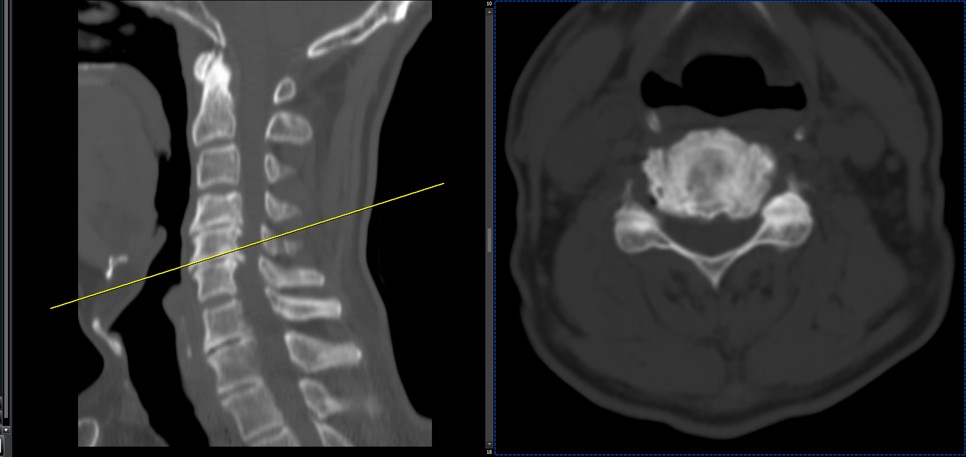

41 years old man presented to my clinic in October 2023 with acute and sever R neck pain with radicular pain to his R upper extremity along C6 dematom since 2 weeks ago. Examination didn’t show any upper motor signs. Was suggested urgent surgery

I ordered EMG/ NCV : showed mild R C6, C7 irritation without any active axonal loss

In his MRI was reported R. para R. IVF Massive extrusion. I decided to control his pain and manage this patient with reevaluation of patient every other session. For 5 sessions i just used acupuncture and laser and IFC and mild adjustments to his R. T3-T7 and mild arthosteem to above and below involved segment. Cervical adjustment considered contraindicated for this patient. From session 6th- 8th i started to use mild/gentle cervical decompression. He used soft cervical collar all the time. His pain decreased by 80 percent

I gave him cervical traction pump to be used 3-5 times per day at home for the next 3 months and i released the patient. He was evaluated every week once for one month and after that every 2 weeks. After 3 month I repeated MRI. Size of the herniated disc was reduced greater than 50 percent. Asked him to do another mri in 6 months

In general: Precise selection of the patients, examination,diagnosis, plan of management, reevaluation and treatment can be done by doctors of chiropractic for the patients with spinal disc herniation and stenosis Moreover giving reasonable time to these kind of patients under direct supervision by their chiropractic doctors can prevent unnecessary surgery. Proper selection of these kind of patients is another important fact that can be done precisely by chiropractors.

MRIs before and after proper management of this patient: